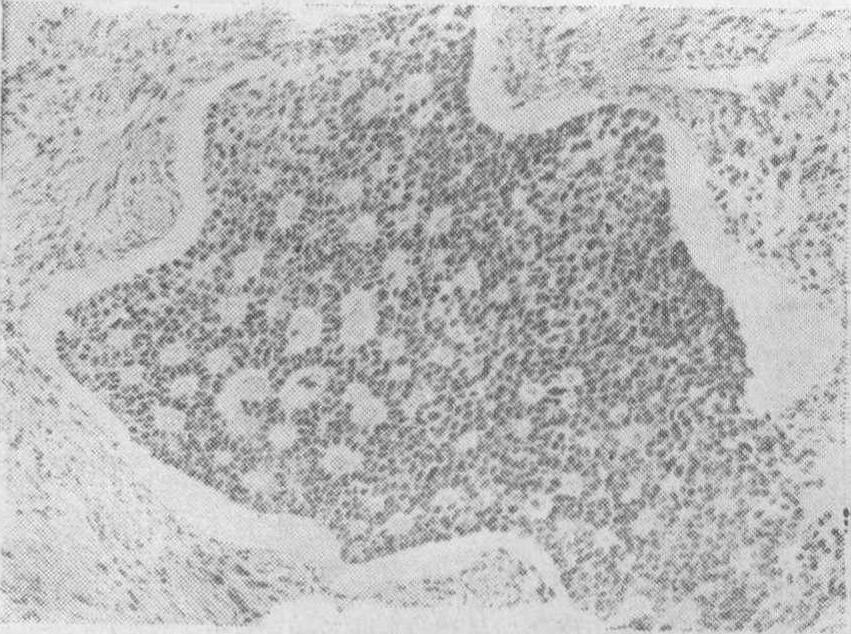

颗粒细胞瘤 是低度恶性的肿瘤,由颗粒细胞组成。大多为单侧性,双侧性者约占5%,肿瘤呈实质,有包膜,晚期可以穿破包膜,切面灰黄色,血管丰富,有时可见有小囊腔、退变或出血区域,触之有海绵感。镜下可见肿瘤由类似卵泡的颗粒细胞构成,排列成大、小卵泡型、腺瘤样型、脑回型、弥漫型等各种形态,以卵泡型最多见。分化好的瘤细胞为胞浆浅染的小多角细胞,大小较一致,细胞核呈圆形,卵圆形或豆形,深染,有时可见与长轴一致的核沟。在卵泡型中可见卡-爱(Call-Exner)小体,它是由颗粒细胞组成的圆形菊花团样结构,中心的空腔内可有嗜酸性液,并可见1~2个退变的裸核,瘤细胞的各型对预后的关系不大,但细胞的分化程度与预后可能有一定的关系。(图1)

图1 卵巢颗粒细胞瘤